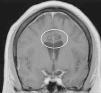

Materiales y métodosSeleccionamos a 8 pacientes pediátricos con TNI bajo un estricto protocolo. Se les realizó electroencefalograma, videoelectroencefalograma y resonancia magnética previo a la cirugía. El síntoma neuroagresivo irreductible fue tratado con cirugía estereotáctica hacia los blancos cerebrales más descritos para agresividad, y posteriormente evaluado mediante la Overt Agressive Scale en el prequirúrgico y a los 6 meses de seguimiento, usando el test de Wilcoxon para el análisis estadístico.

Materials and methodsEight pediatric patients met strict criteria for IND and were enrolled in this study. Electroencephalography (EEG), video electroencephalography (VEEG) and magnetic resonance imaging (MRI) were performed in all patients prior to surgery. Irreducible neuroagressive symptom was approached by lesional therapy based on most described targets for this disorder and assessed by The Overt Agressive Scale (OAS) pre-operatively and 6 months following surgery, using Wilcoxon test for statistical analysis.